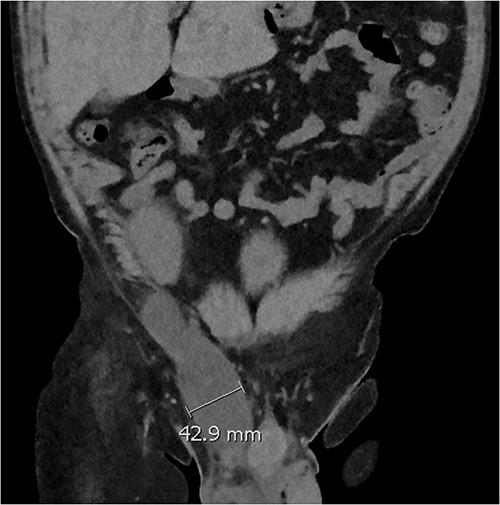

Coronal CT image showing a dominant fluid collection extending off the lower pole of the transplant kidney into the right inguinal canal.

Three weeks postoperatively, the patient noticed a progressively enlarging right groin mass and associated discomfort. His examination was notable for a firm non-pulsatile non-reducible inguinal mass with no bowel sounds. He proceeded to have a CT Kidney, Ureter, Bladder (KUB), which revealed a small amount of perinephric collection (20 Hounsfield unit) marginating the posteromedial aspect of the transplant lower pole with a further fluid collection distending the right inguinal canal (10 Hounsfield unit) (see Fig. 1). The inguinal fluid pocket was localized with bedside ultrasound and 30 ml of clear fluid was aspirated with immediate symptom relief. The patient noticed reaccumulation of the fluid after a week and became symptomatic of pain again by the end of the third week.